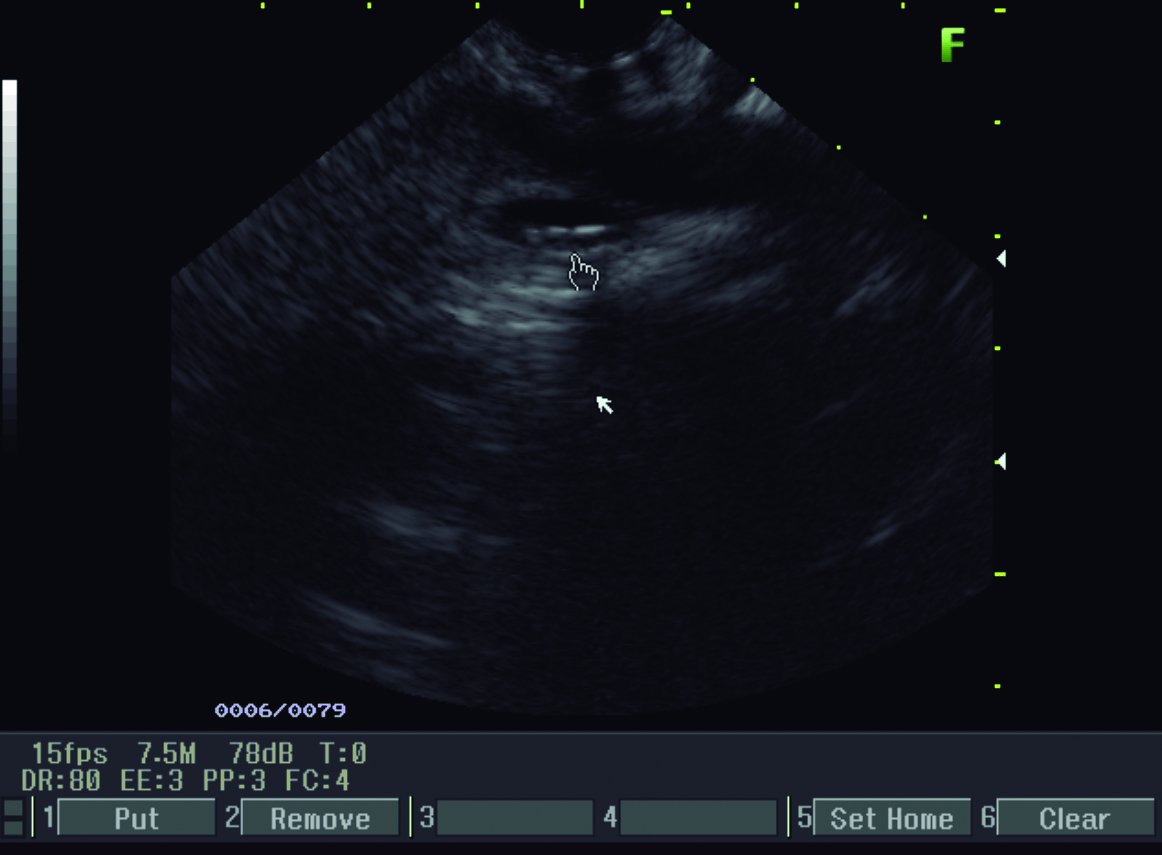

Se interroga a la paciente y refiere haber sido estudiada previamente con una colangiografía por resonancia magnética tres meses previo a la consulta en otro centro hospitalario. En ese momento la vía biliar principal no estaba ocupada. Retrospectivamente se identificaron los parásitos en el tubo digestivo proximal (Fig. 4 y 5).

Figura 4. Resonancia Magnética

a y b) Imágenes en plano coronal potenciadas en T2 sin saturación grasa. A nivel de asas yeyunales proximales se identifican los parásitos

como imágenes lineales ligeramente hiperintensas con un área central hipointensa (*).

Figura 5. Colangiografía por Resonancia Magnética - Reconstrucción

Se visualiza vía biliar intra y extrahepática de calibre habitual, sin defectos de relleno.

La resonancia magnética es una excelente modalidad no invasiva para diagnosticar la presencia de parásitos en la vía biliar. En imágenes ponderadas en T1, los gusanos se ven como estructuras tubulares lineales ligeramente hiperintensas con un área central hipointensa y en la colangiografía por resonancia se visualizan como defectos lineales de relleno hipointensos en el tracto biliar. (4, 9, 10)